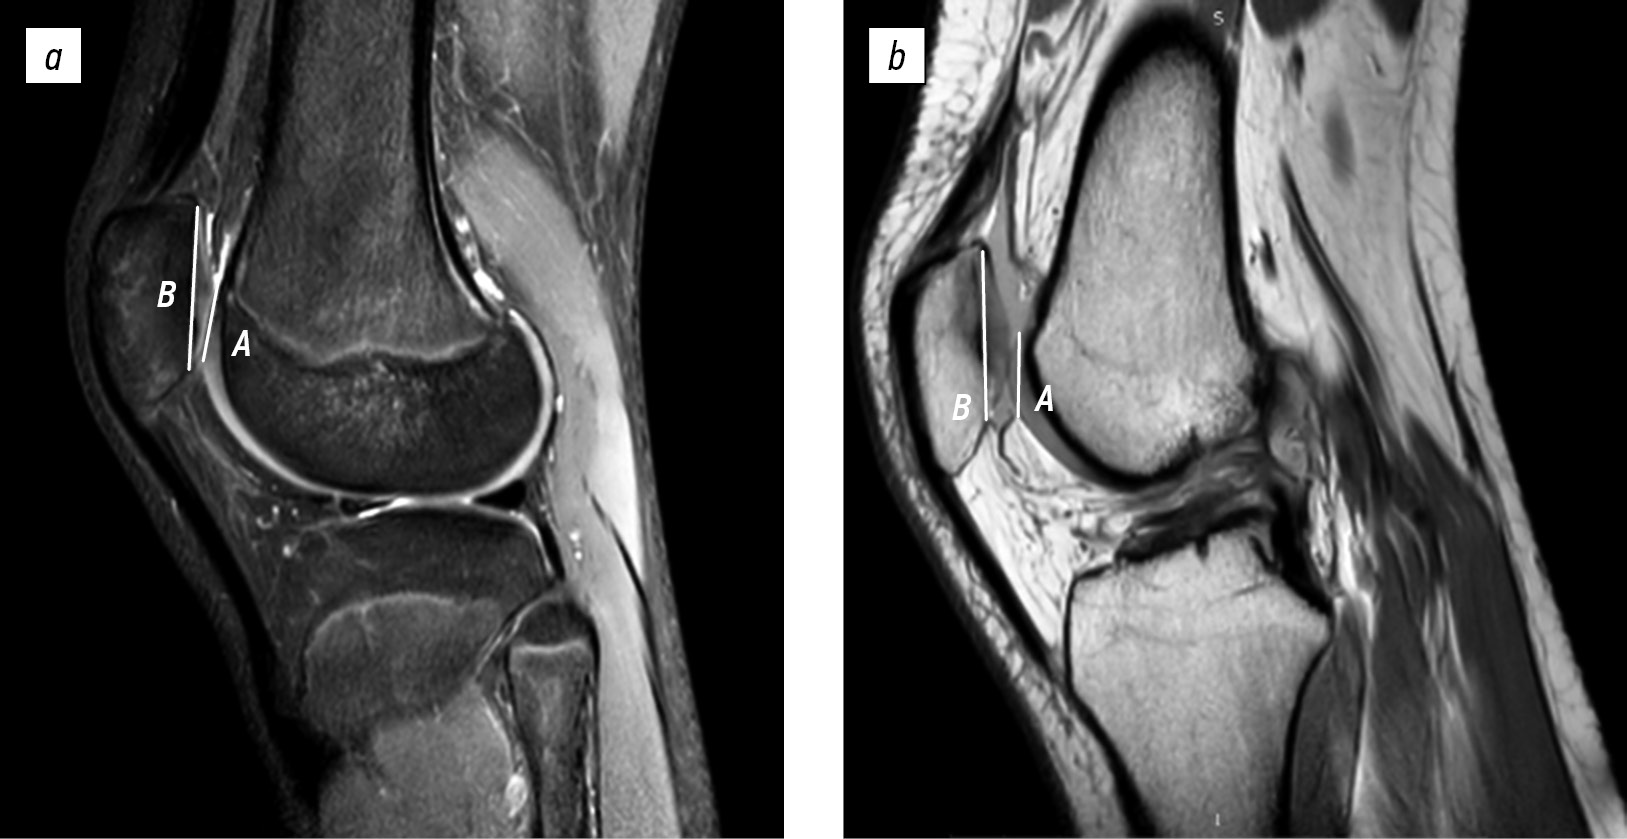

Lateral trochlear inclination was assessed using the first axial image on which the articular cartilage was visible. The inclination angle between the lateral condylar line and posterior femoral condylar line was measured. A line tangent to the subchondral bone of the posterior surfaces of the femoral condyles was intersected with a line tangent to the subchondral bone of the lateral surface of the trochlear groove. An inclination angle of <11° indicated trochlear dysplasia (Fig. 1) [12].

Fig. 1. Lateral trochlear inclination on magnetic resonance imaging in a 15-year-old female patient with patellar instability (1.2°) (a) and in a 17-year-old female patient with anterior cruciate ligament injury (21°) (b). A, line tangent to the lateral facet; B, line tangent to the posterior condylar line.